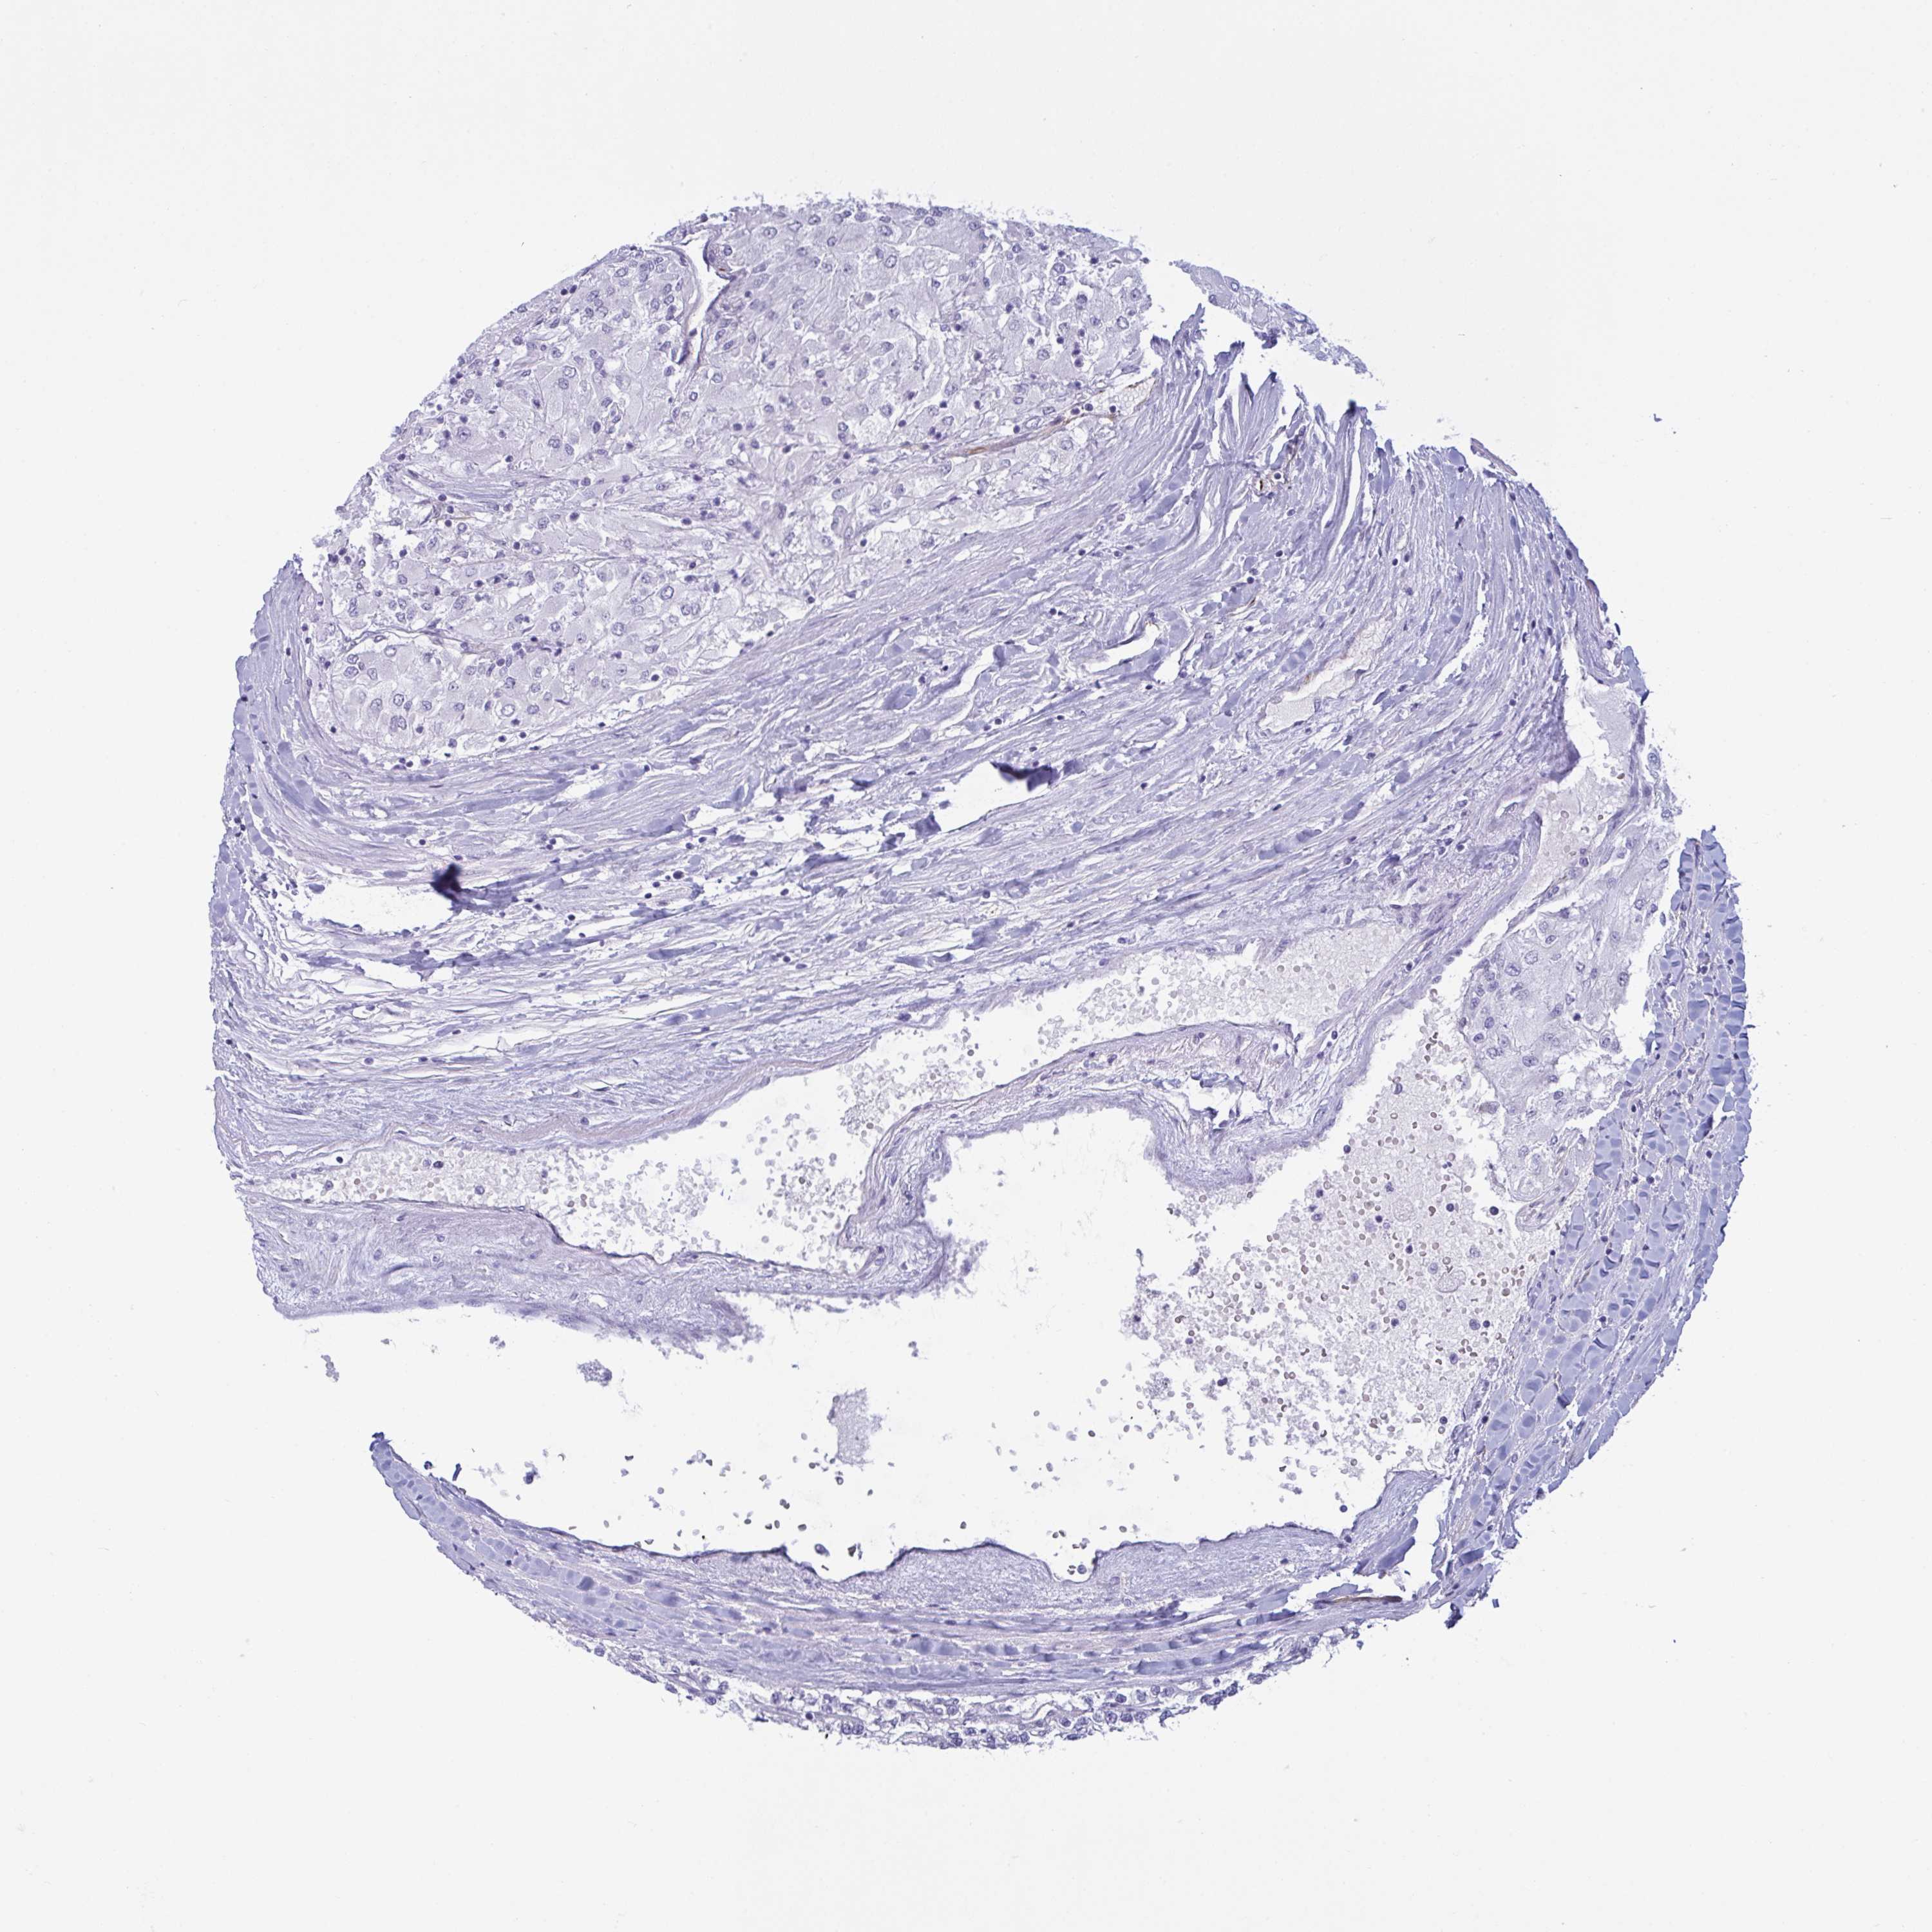

Renal cancer

Kidney chromophobe